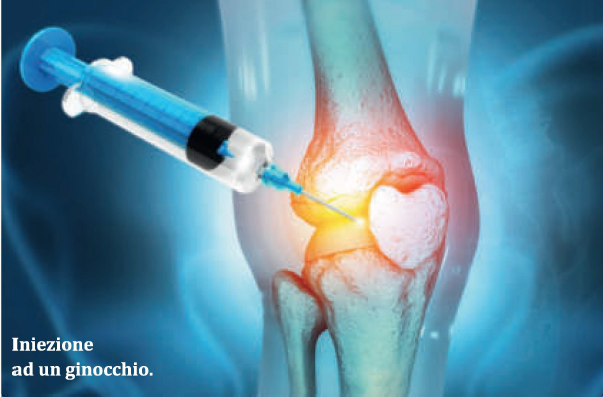

Cellule mesenchimali

Negli ultimi anni si è sviluppata la medicina rigenerativa, il cui obiettivo è quello di “riparare” cellule, tessuti ed organi utilizzando le cellule staminali.

In ortopedia, una delle tecniche rigenerative più efficaci si basa sull’utilizzo delle cellule mesenchimali, un particolare tipo di staminali che stimolano la ricostruzione della cartilagine.

Terapie Infiltrative

• Acido ialuronico

• Terapia del dolore (infiltrazioni mirate, anti-infiammatori)